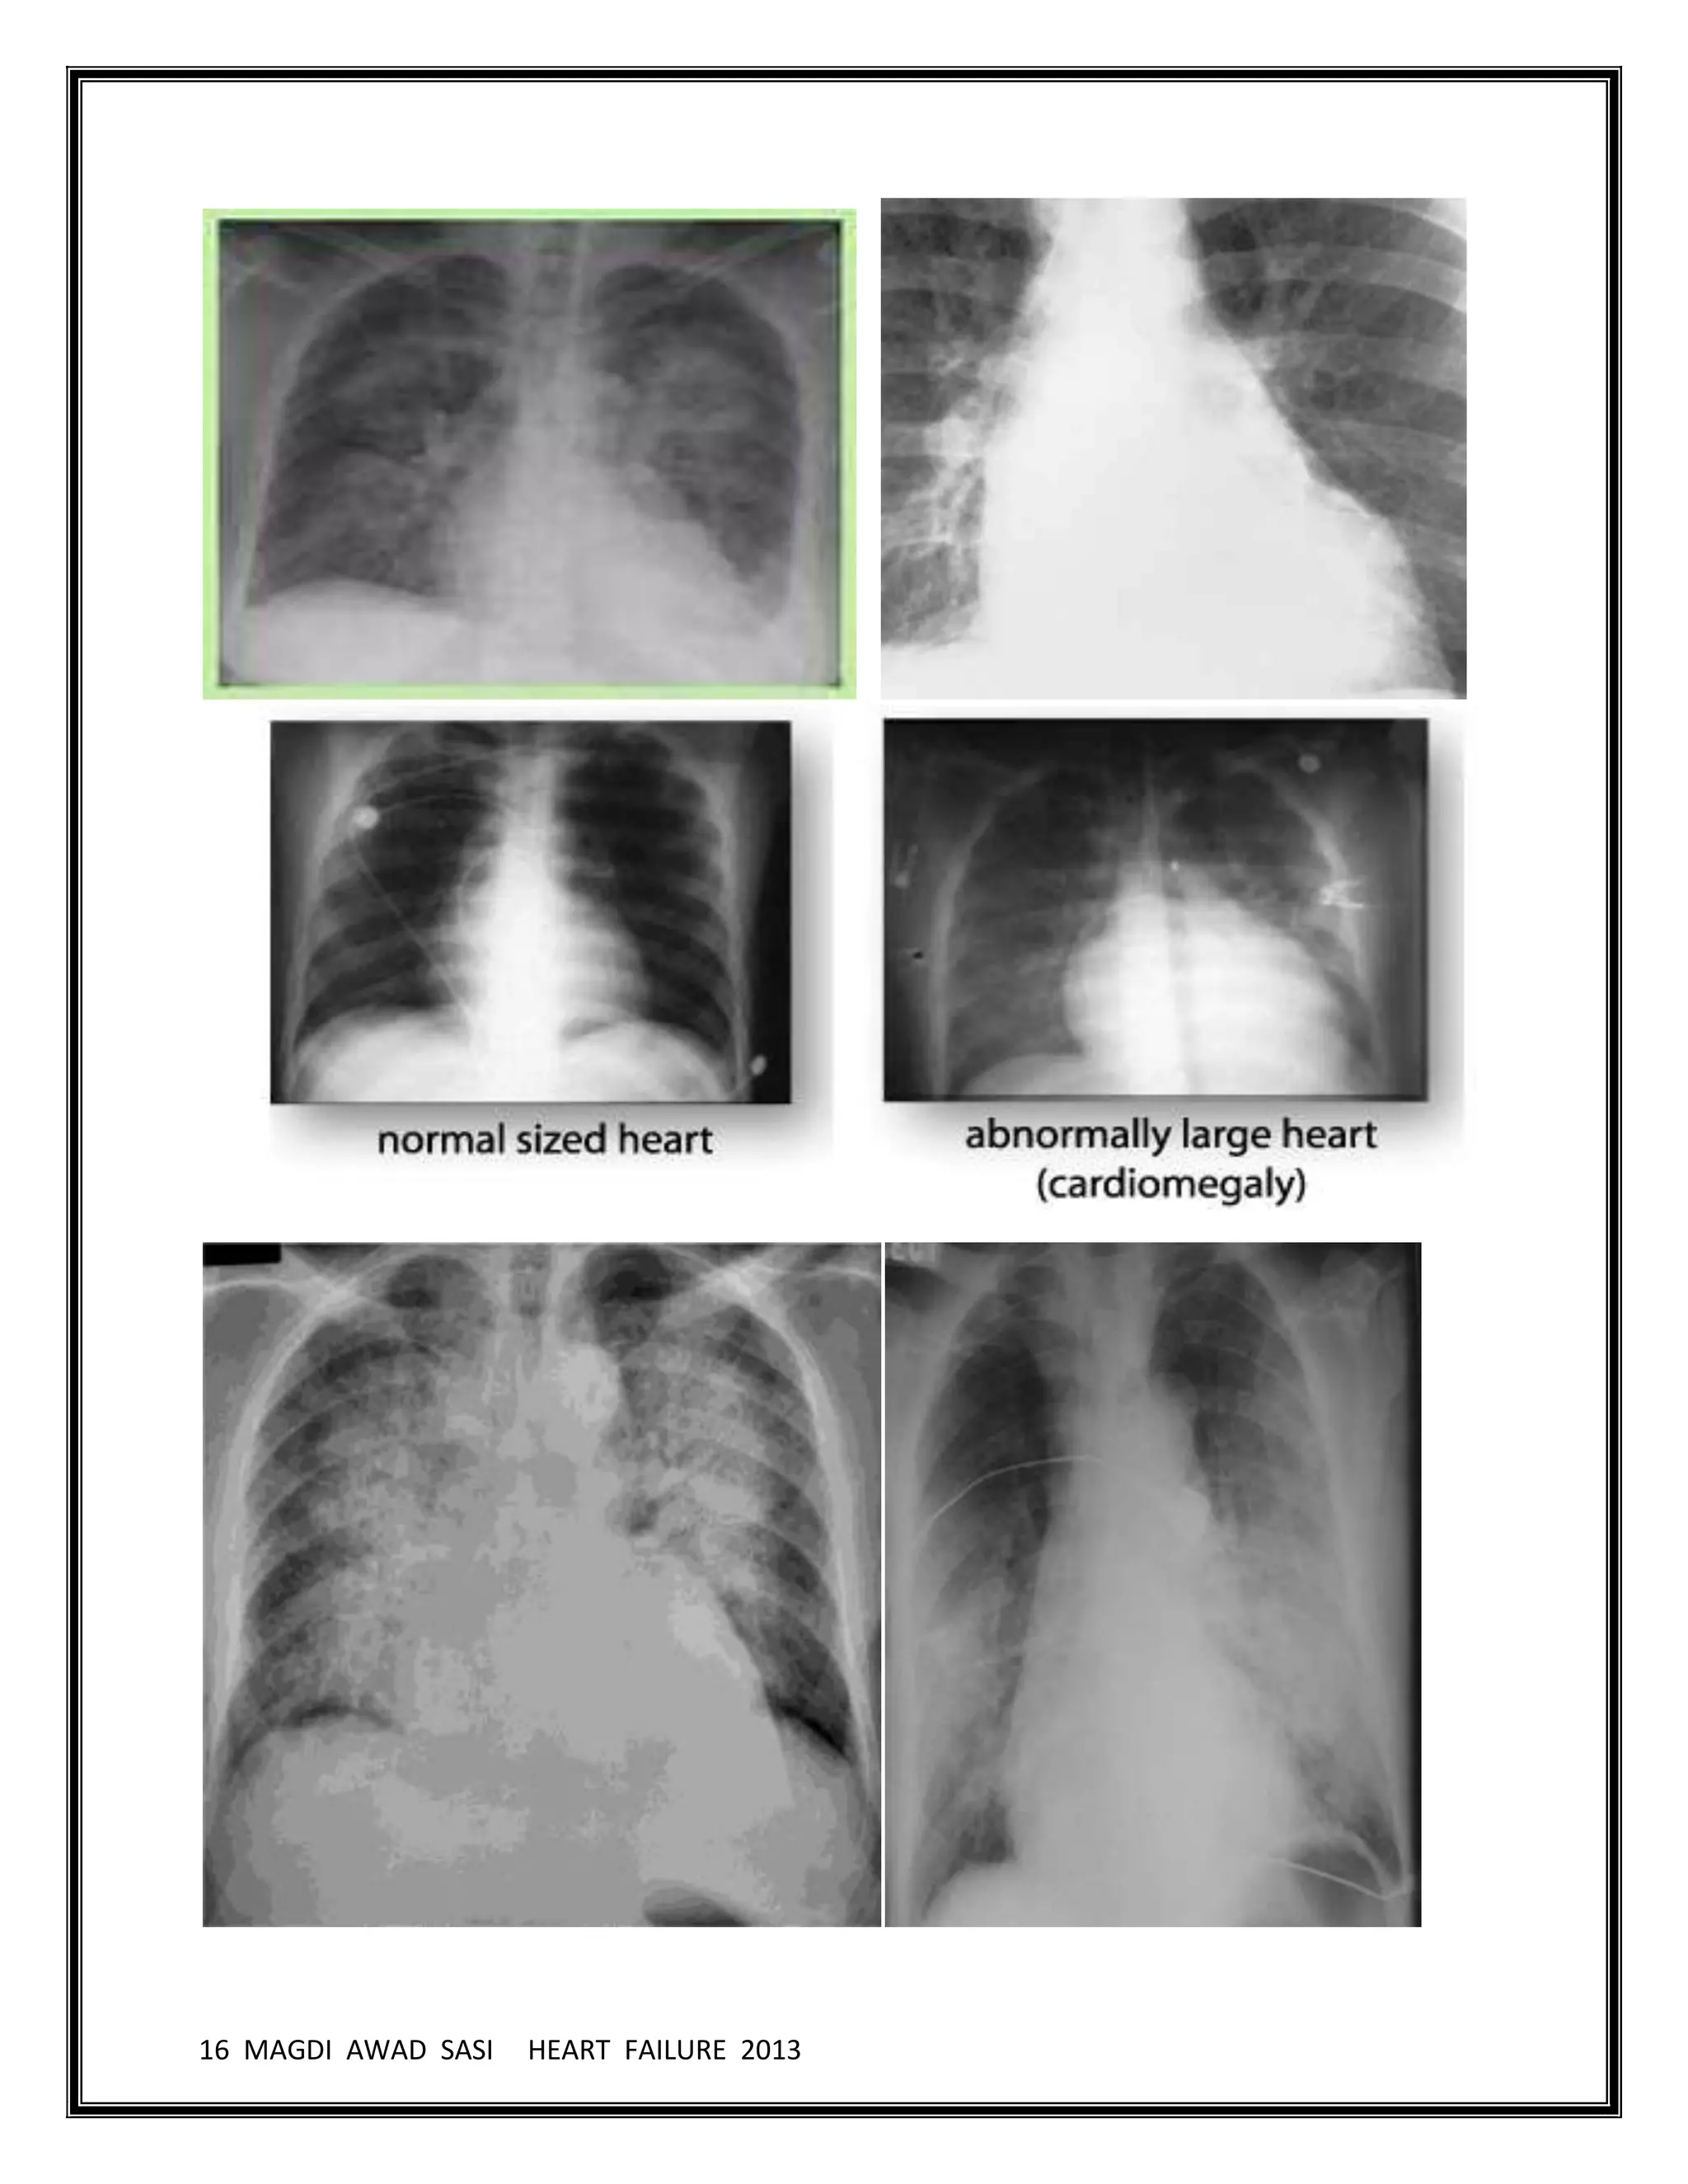

CXR

Cardiomegaly

Vascular redistribution

Kerley B lines

Interstitial edema

Peri-bronchial “cuffing”

Effusions

Chest radiographs in patients with abrupt onset are usually helpful but can be

limited because a delay of as long as 12 hours is possible from the onset of

dyspnea due to acute heart failure to the development of classic abnormal

findings on radiographs.

Classic radiographic findings demonstrate cardiomegaly (in patients with

underlying CHF) and alveolar edema with pleural effusions and bilateral

infiltrates in a butterfly pattern. The other signs are loss of sharp definition of

pulmonary vasculature, haziness of hilar shadows, and thickening of

interlobular septa (Kerley B lines).

In long standing biventricular chronic heart failure, chest radiographs may only

show cardiomegaly without alveolar edema or pleural effusions due to

adaptive lung mechanism with increased arterial vasoconstriction and

lymphatic drainage.